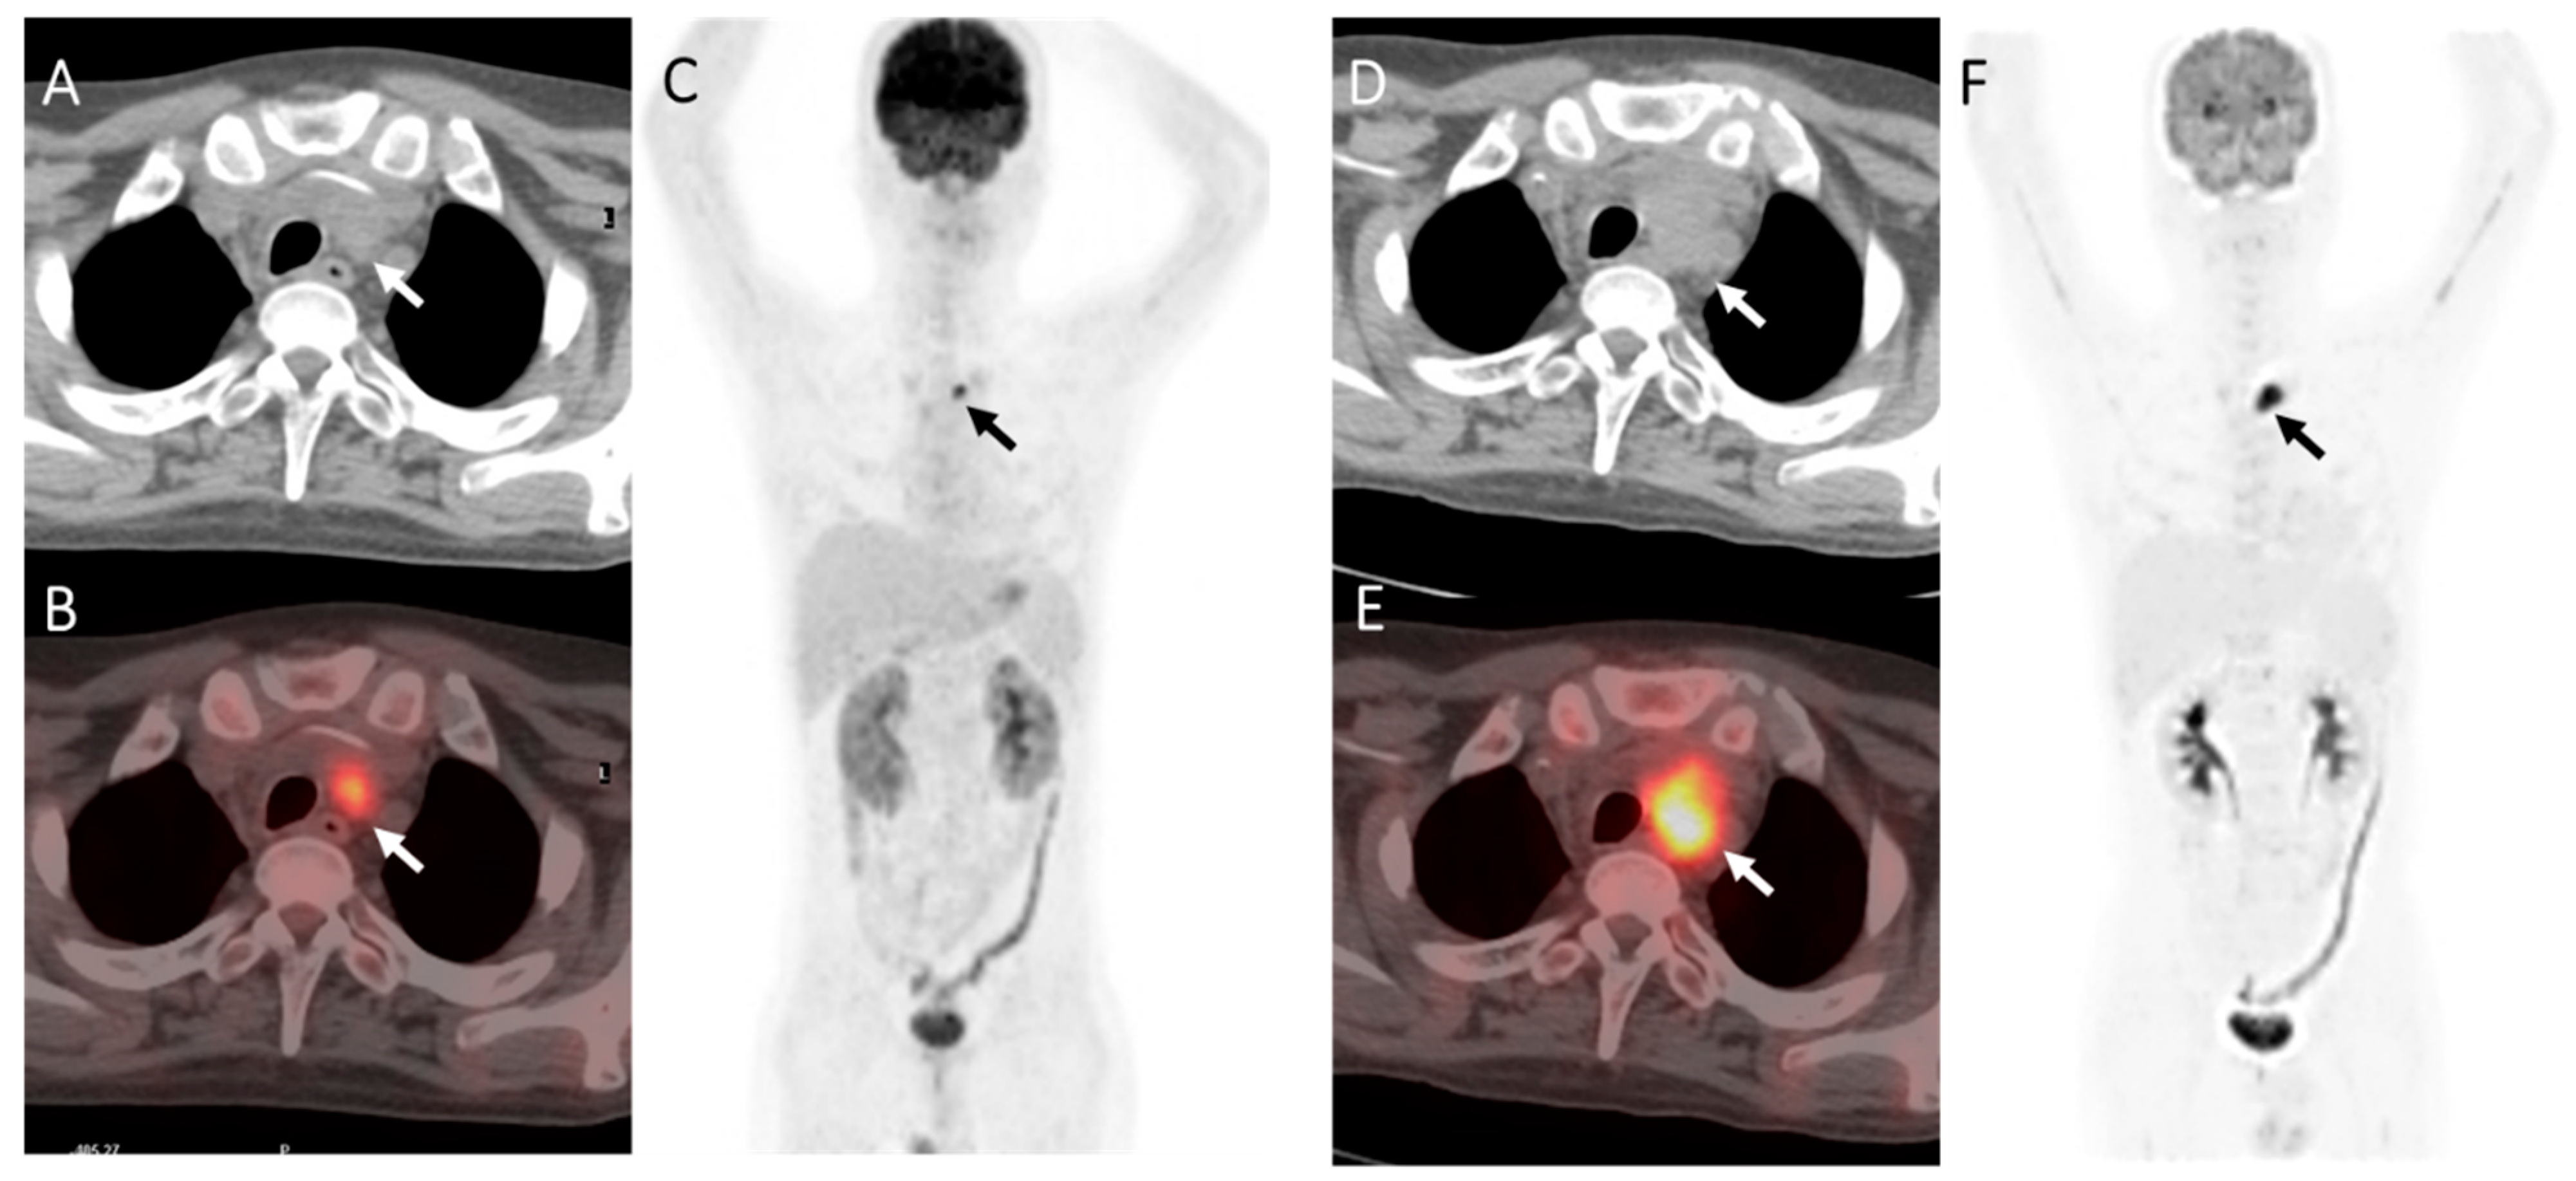

Figure 3.

A case of T-Lymphoblastic lymphoma of the mediastinum in a 30-year-old male. The patient was treated with chemotherapy and achieved complete remission. The patient then received allogeneic SCT and underwent 18F-FDG PET-CT 5 months after transplantation for assessment. (A–C): PET showed an FDG-avid lesion in the upper mediastinum (arrow), about 1.7 * 1.2 cm2 in size, SUVmax7.61 (DS = 5). (D–F): A close follow-up PET imaging was carried out 1 months later with no treatment. It showed the upper mediastinum lesion (arrow) increased both in size (2.9 * 2.2 cm2) and 18F-FDG uptake (SUVmax10.85). Finally, it was clinically determined as a relapse.